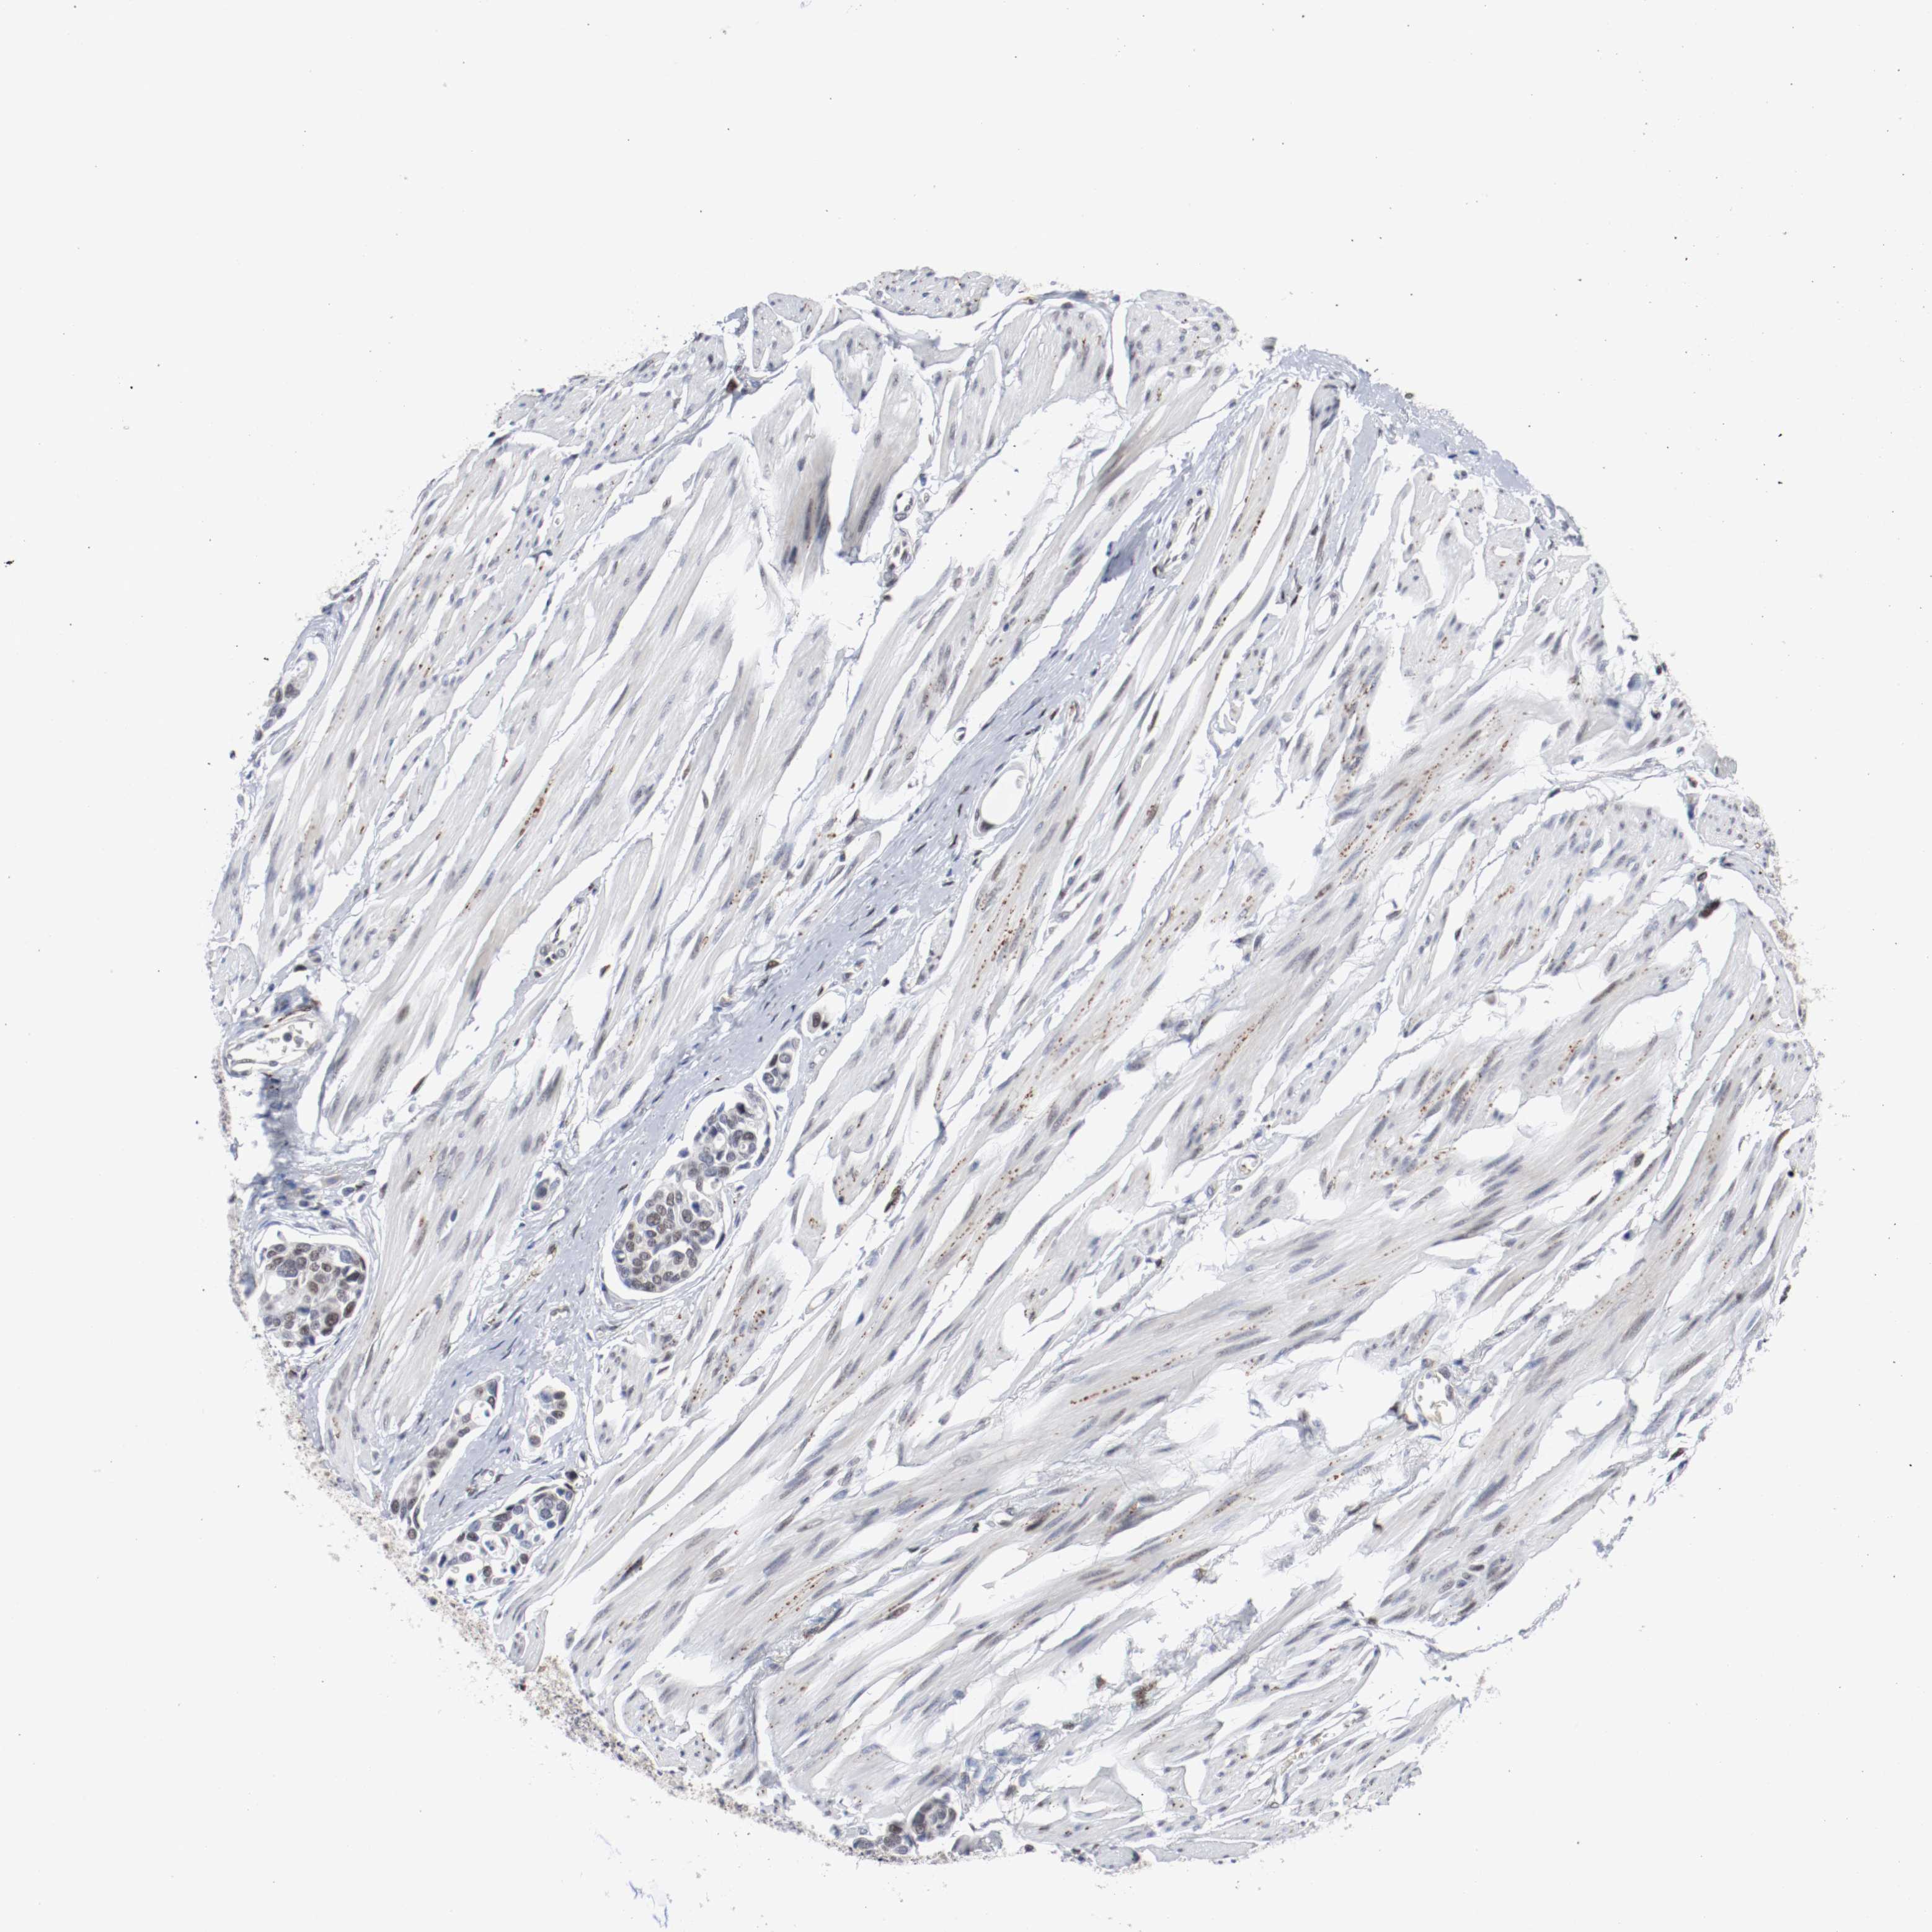

UROTHELIAL CANCER - Protein expressioni

A mouse-over function shows sample information and annotation data. Click on an image to view it in a full screen mode. Samples can be filtered based on level of antibody staining by selecting one or several of the following categories: high, medium, low and not detected. The assay and annotation is described here.

Antibody stainingi

Antibody staining in the annotated cell types in the current human tissue is reported as not detected, low, medium, or high, based on conventional immunohistochemistry profiling in selected tissues. This score is based on the combination of the staining intensity and fraction of stained cells.

Each image is clickable and will lead to virtual microscopy that enables deeper exploration of all samples and also displays staining intensity scores, fraction scores and subcellular localization as well as patient and tissue information for each sample.

Antibody HPA063029

Antibody CAB005268

Urothelial carcinoma, High grade